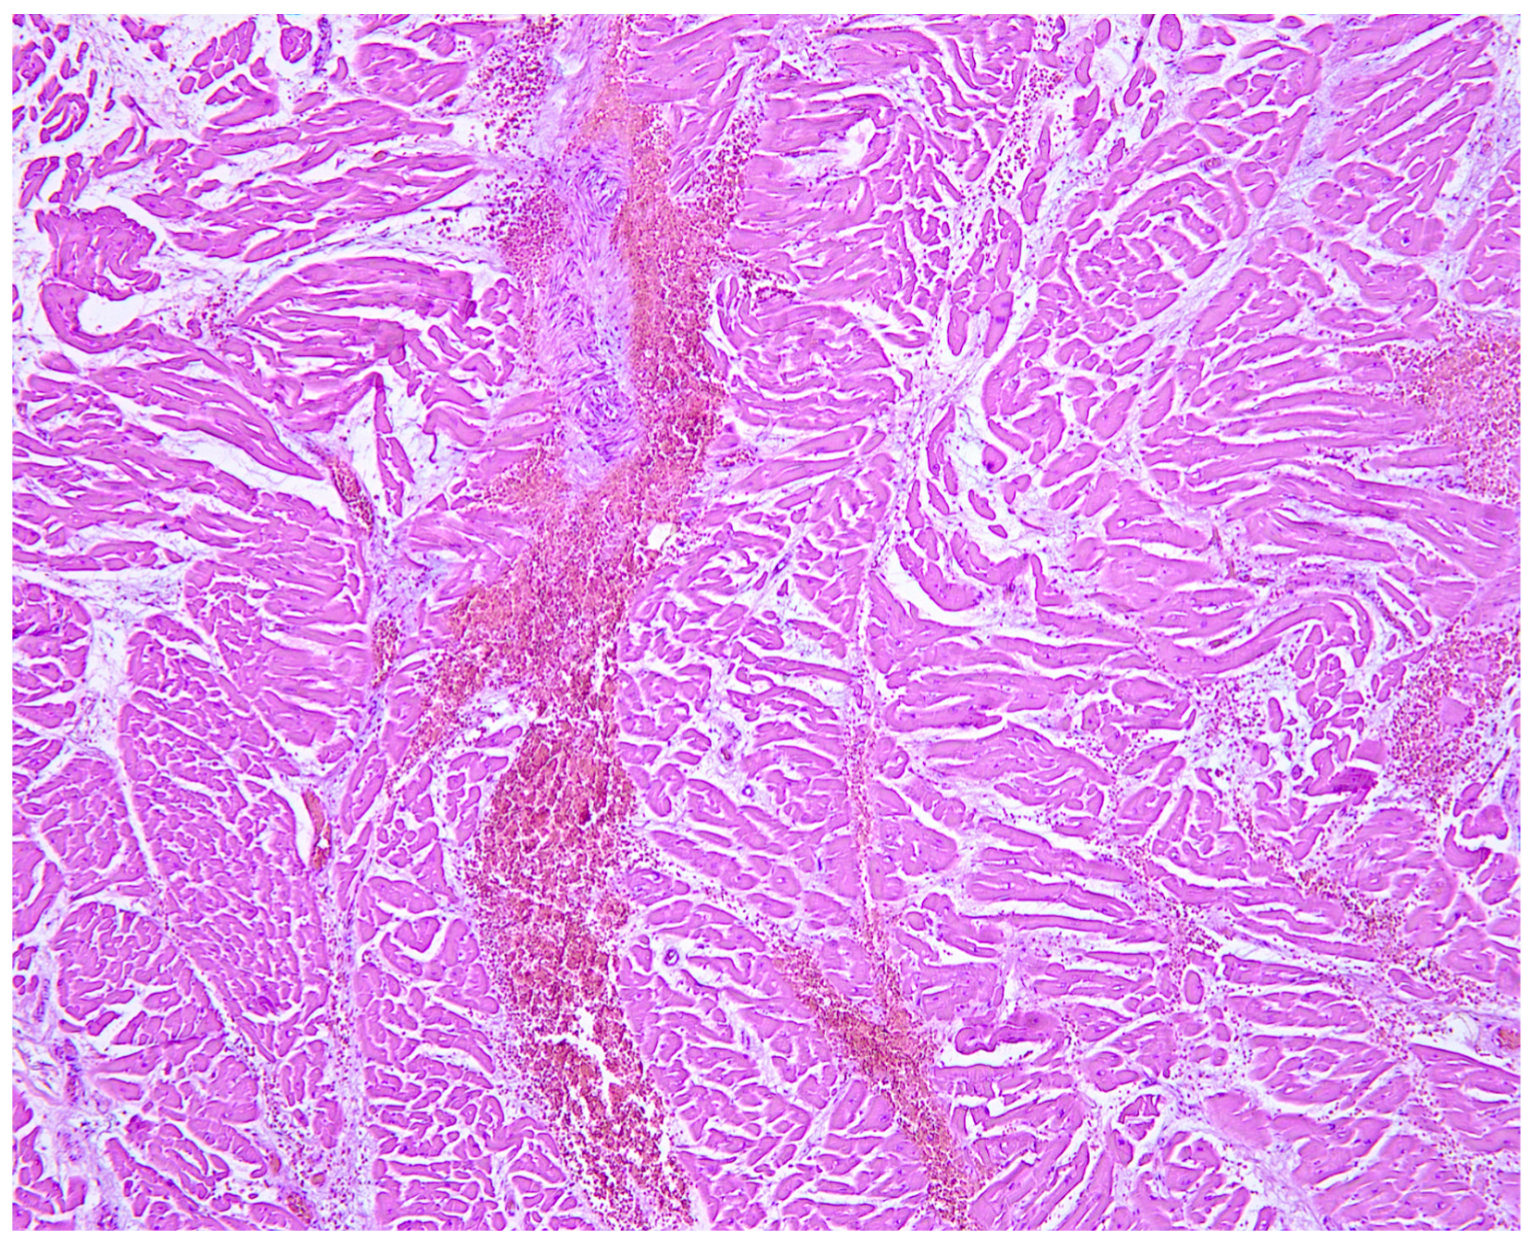

Impact of Cardiac Surgery Scar on Heart Rupture Following a Fall from Height

Napoletano, G.; Treves, B.; De Paola, L.; Del Duca, F.; Ghamlouch, A.; Frati, P.; Maiese, A. Impact of Cardiac Surgery Scar on Heart Rupture Following a Fall from Height. Diagnostics 2024, 14, 2472. https://doi.org/10.3390/diagnostics14222472